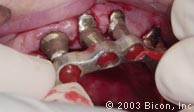

就位在研磨基台上的六颗独立的金属帽。 |

![]() |